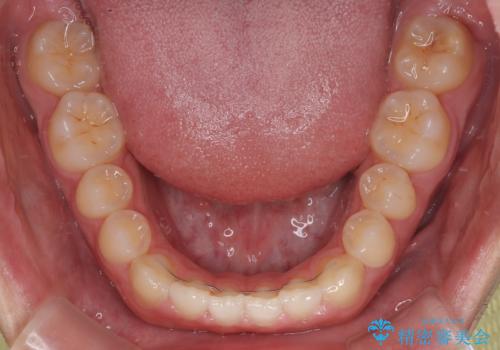

マウスピース矯正特有の奥歯への圧下により、一時的に噛みにくさを感じる場面もありましたが、

装着時間の調整と経過観察を行うことで症状は改善し、スムーズに治療を完了しました。